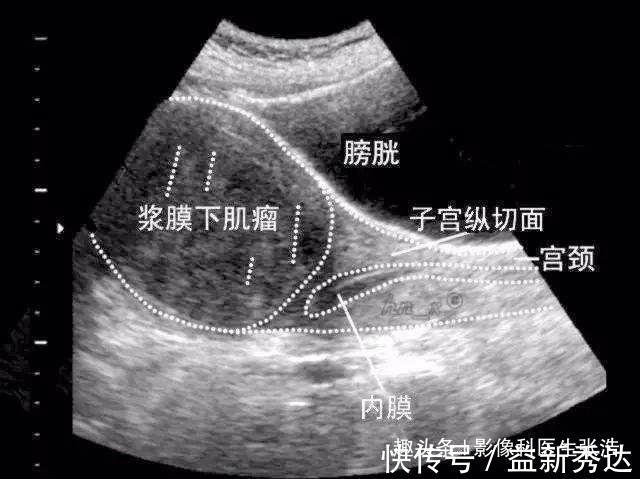

上图是超声检查发现的子宫肌瘤,体积比较大。出现子宫肌瘤会有哪些临床表现呢?子宫肌瘤多为良性,部分会伴有小腹痛、白带增多、月经量多等症状,较大的肌瘤(直径在5公分以上)会在腹部触摸到包块,特别大的肌瘤是会影响到子宫的功能的。